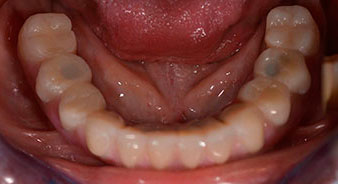

L'empreinte et l'enregistrement de l'occlusion ont ensuite été effectués afin que le prothésiste dentaire puisse commencer à réaliser la restauration provisoire. Celle-ci a été vissée le jour même (Fig. 17 et 18).

Après ostéointégration, l'empreinte finale des implants a été effectuée et la prothèse finale a été fabriquée en conséquence (Fig. 19 et 20). À cette étape, le praticien et le patient ont pu décider ensemble d'utiliser une facette dentaire en céramique ou en acrylique et une armature en zircone ou en métal. Dans ce cas, l'équipe du Dr Pascu a opté pour une facette dentaire en acrylique en raison du pronostic incertain de la denture maxillaire et du fait que la dent 24 est extrusée. Ce type de facette est plus facile à ajuster et peut donc être modifiée selon la nouvelle situation maxillaire.